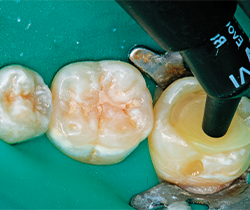

Fig. 1 Fig. 2

Under rubber dam isolation (Hygenic Non-Latex Dental Dam, Coltene Whaledent), the caries were removed and the teeth restored one quadrant at a time. A carbide bur was used to remove caries, followed with a diamond to bevel the cavosurface margins and finally with a round bur to excavate the deepest portion of the decay (Figs. 6-7).

The bevel on the cavosurface margin allows for increased esthetics for the materials to have a chameleon effect with the underlying enamel. The resultant cavity preparation revealed preparations that were in excess of 4 mm deep in all prepared teeth. Once the caries were completely removed, the dentin and enamel were particle abraded with a PrepStart™ (Danville) with 40 micron aluminum oxide to homogenize the dentin, creating a uniform smear layer of the dentin forming the ideal interface for dentin bonding. The decision was made to use Tetric EvoCeram Bulk Fill (Ivoclar Vivadent) composite restorative.